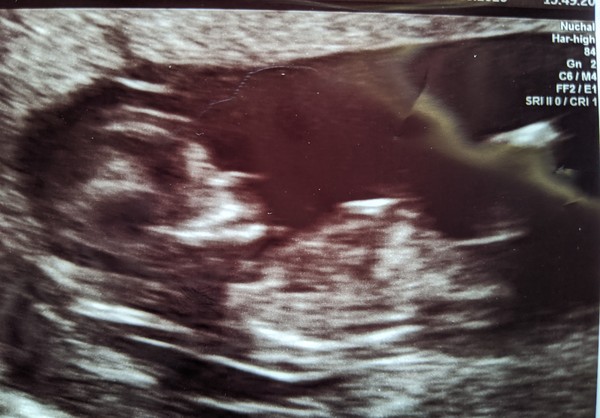

Scan was all good! 12 +3 today. The photo is dreadful though! She had the option to print so many decent ones and she printed a shocker - just looks like a smudge!

Smilingdonkey · 26/08/2020 18:10

Here's the terrible photo ...